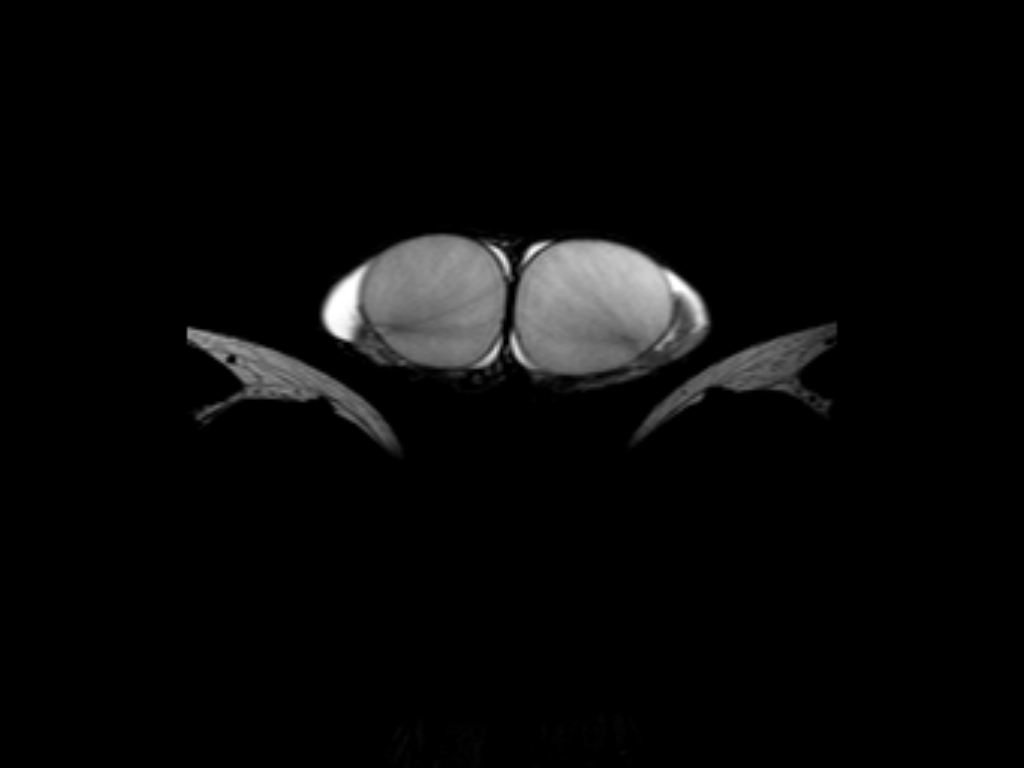

Χαρακτηριστικές Εικόνες MRI Οσχέου

i) T2W TSE

Βασική Ακτινοανατομία MRI Οσχέου